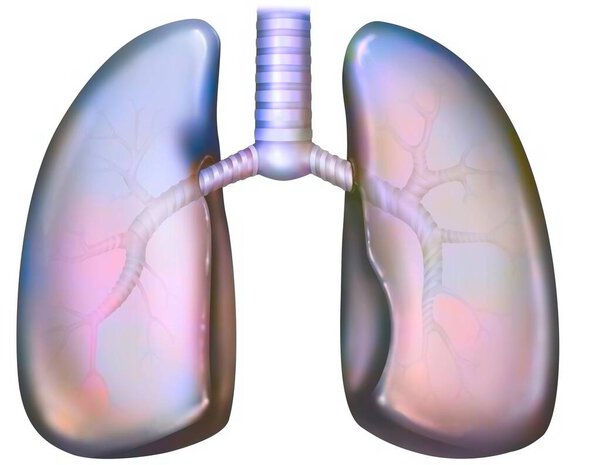

- Рак легких курильщика (с наличием депозитов смолы в бронхах).

Рак легких курильщика (с наличием депозитов смолы в бронхах).

Рак легких курильщика (с наличием депозитов смолы в бронхах).